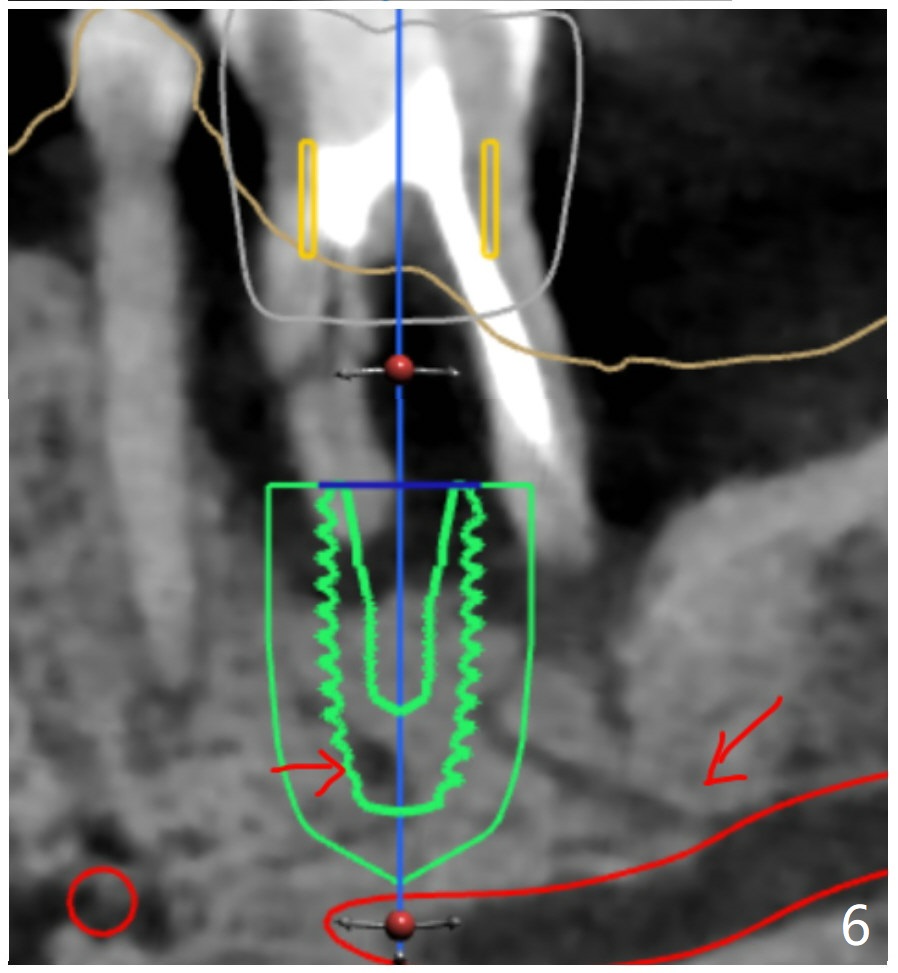

Placement M

When the patient finally agrees to have the tooth #19 to be extracted for implant (Fig.1), there is also mesial bone loss associated with mesial root fracture (Fig.2). To avoid truncation of the blood vessels toward the apex of the tooth #20 (Fig.2 black shadow and red line; Fig.4-6 (lab design) red symbols), a 5x10 mm implant will be placed more distal than the earlier design when the septum was present. The implant is also to be placed slightly higher than the native bone to improve crown/implant ratio; i.e., equical to the buccal, lingual and distal crests (Fig.3-6). Allograft will be placed in the gaps. After distal placement with minor axial change, new treatment plan is born. Return to Lower Molar Immediate Implant, Prevent Molar Periimplantitis (Protocols, Table), Trajectory, Weichat Xin Wei, DDS, PhD, MS 1st edition 01/14/2019, last revision 12/28/2019